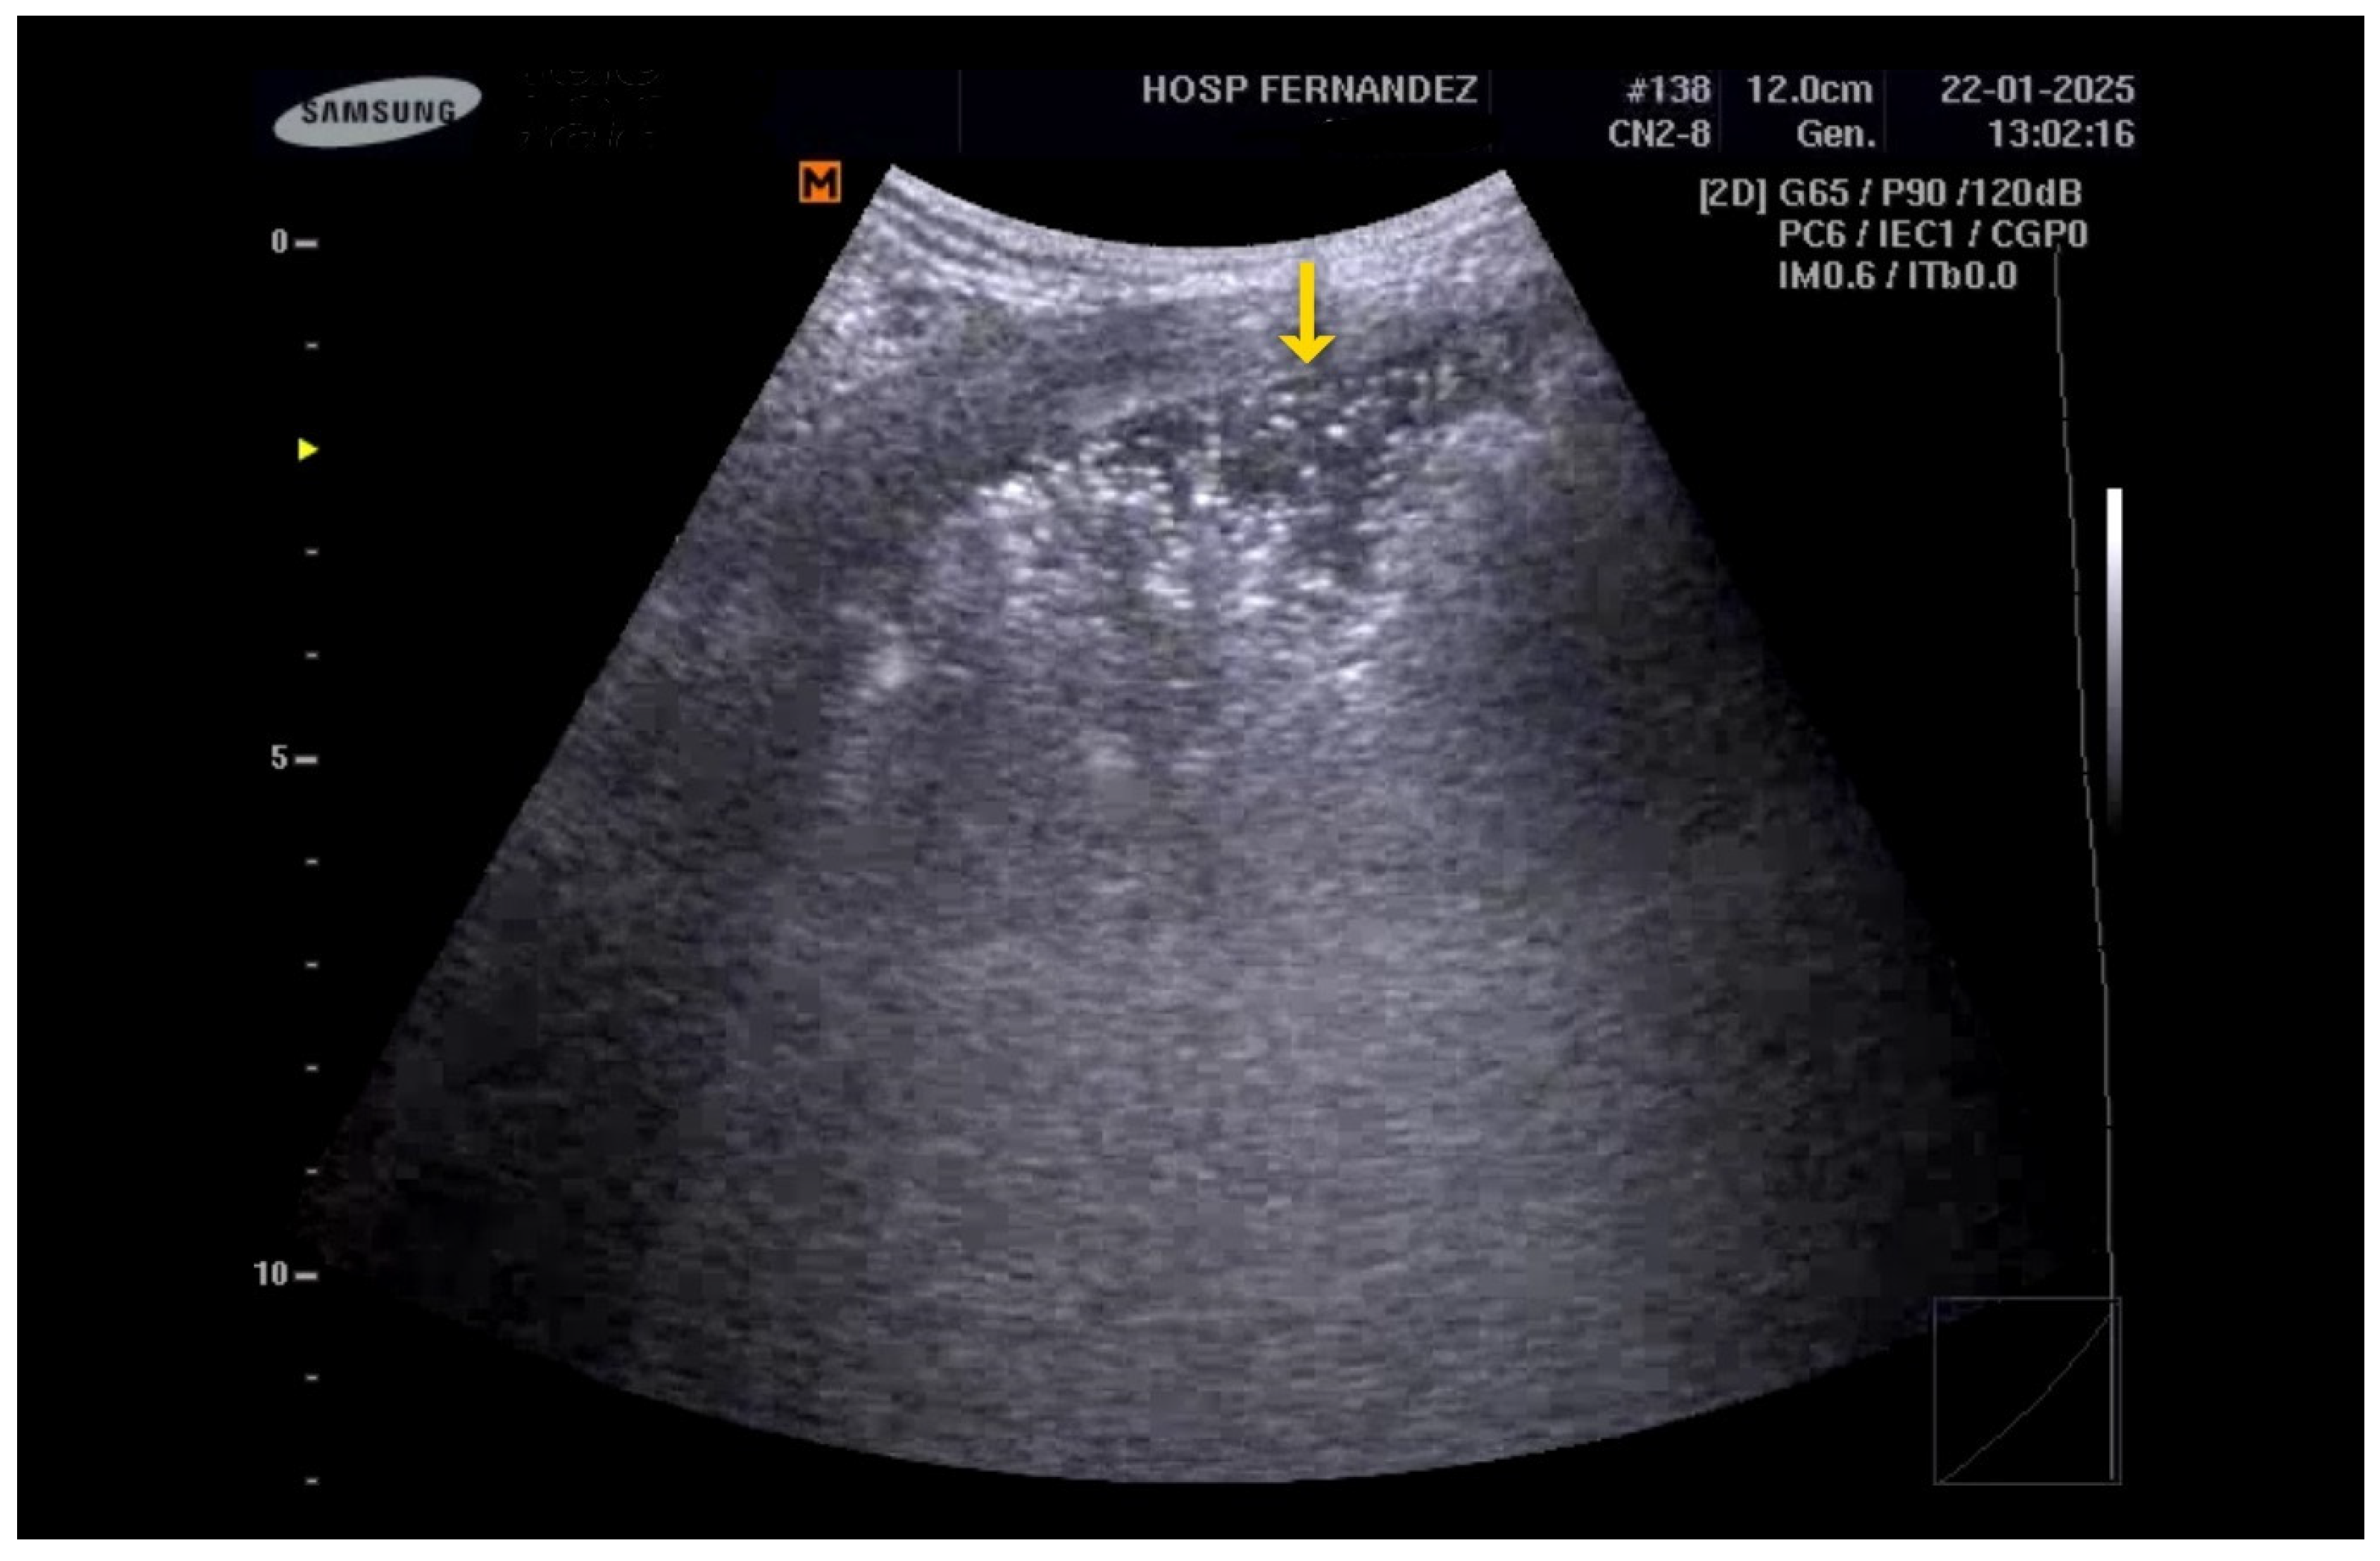

5. LUS for the Detection of Consolidations

- Anterior subpleural consolidations;

- Abnormalities in the pleural line (e.g., fragmented, thickened, or irregular pleural line);